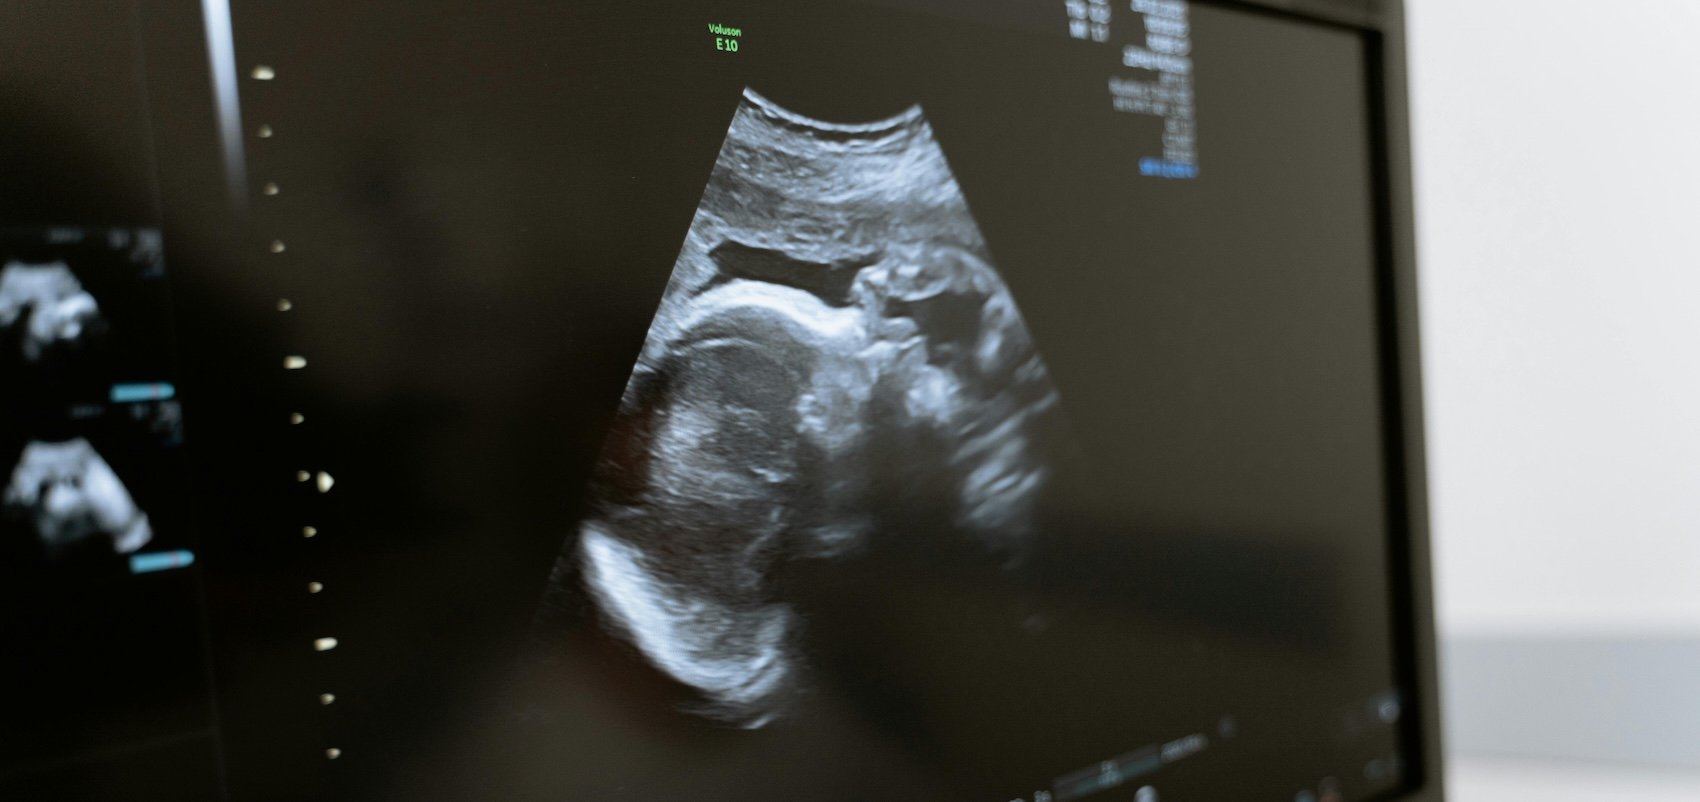

And then there’s the inconvenient fact that IVF produces more embryos than can be “used.” The term itself introduces the unsettling notion that human life is something we make available to ourselves for our own purposes—or disposal. When it comes to current technology, if the goal is eugenic selection, there’s no way around the need to produce embryos outside the womb so that the biological material for ­genetic ­testing can be gathered. And they must be frozen, held in reserve so that, once test results are received, the parents (owners?) of the embryos can make their ­selections.

Siddiqui reports that she and her husband have ­sixteen embryos on ice, ready for “when the time is right.” She wants two boys and two girls, whom she will pick out of the embryo tray, guided by the Orchid reports as to which enjoy the most genetically auspicious profiles. (If you’re starting to feel queasy reading this, you’re not alone.)